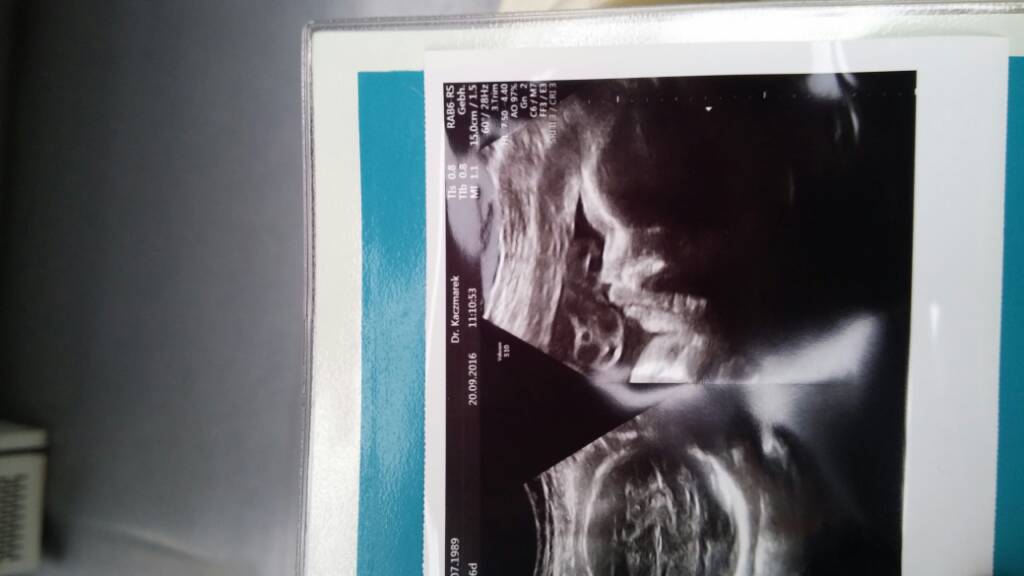

a ja sie we wtorek wybieram do trzeciego gina. Tesciowa mnie umowila do swojej znajomej. Zobaczymy co powie na moje wyniki. Narazie dobre jest to ze powiedziala ze wypisze mi wszystkie mozliwe skierowania na badania na nfz.